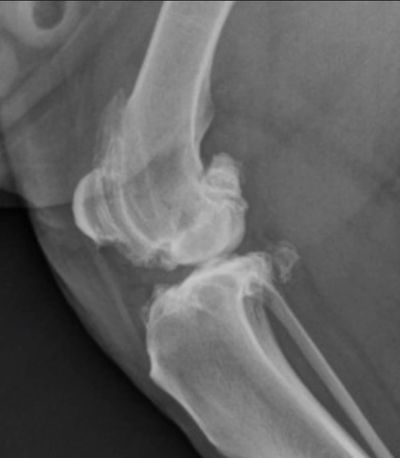

● Osteoarthritis (OA) and related pain affect 15-25% of dogs

● OA affects 80% of dogs aged 8 years and older